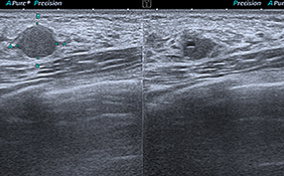

What Happens After You Find a Fibroadenoma

While these often require no treatment, a biopsy or removal is necessary in some cases.

Can Fibroadenomas Turn Into Breast Cancer?

Found in women’s breast tissue, complex fibroadenomas may increase the risk of breast cancer.